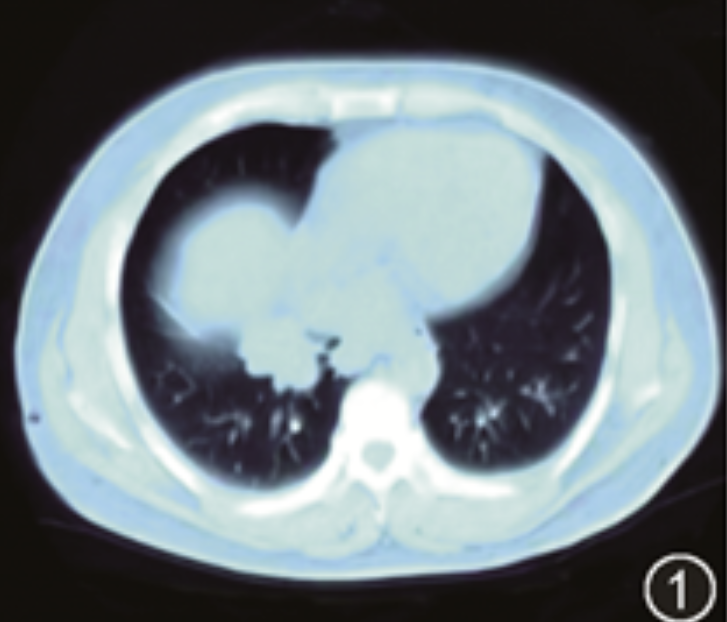

患者男,41岁,因“发现右肺占位2个月,胸闷气短1个月余”于2024年6月4日入院。患者自2个月前(2024年4月5日)因泌尿系结石拟行手术治疗,在当地医院术前胸部CT检查中发现右肺下叶占位(图1)。后行支气管镜检查,提示右肺下叶内基底段隆起性肿物,阻塞管腔,遂行右下肺叶切除术,术后病理示:肉芽肿性炎,小灶脓肿形成,不除外特殊感染性疾病。结合病理回报,当地医院考虑结核可能性大,给予四联抗结核药物(左氧氟沙星、异烟肼、吡嗪酰胺、乙胺丁醇)治疗,于2024年5月6日出院。出院后,患者间断胸闷、气短、咳嗽、咳少量白痰,易咳出,但无发热。居家过程中,患者发现左前胸壁、后背中下部及颅顶等部位新发肿块,呈进行性增大。1周前,患者复查胸部CT示(术后36 d):右肺下叶切除术后改变,右肺上中叶炎症,右腋窝淋巴结肿大,右侧胸腔少量积液,双侧胸膜局部增厚,左侧胸壁及胸骨软组织密度影;完善头颅CT示:左侧顶部皮下占位伴骨质破坏,考虑转移瘤可能,为求进一步诊治入我院。既往有慢性乙型病毒性肝炎病史20年,未规律诊治,右肾结石体外碎石术及双侧输尿管支架置入术后1个月,否认外伤、输血史,否认药物、食物过敏史,无吸烟史,无酗酒史。从事牛羊饲料运输工作3年,常有牛羊接触史。否认工业毒物、粉尘及放射性物质接触史,无性病冶游史。家族史无特殊。

图1 2024年4月5日外院术前胸部CT检查时首次发现右肺下叶实变团块影